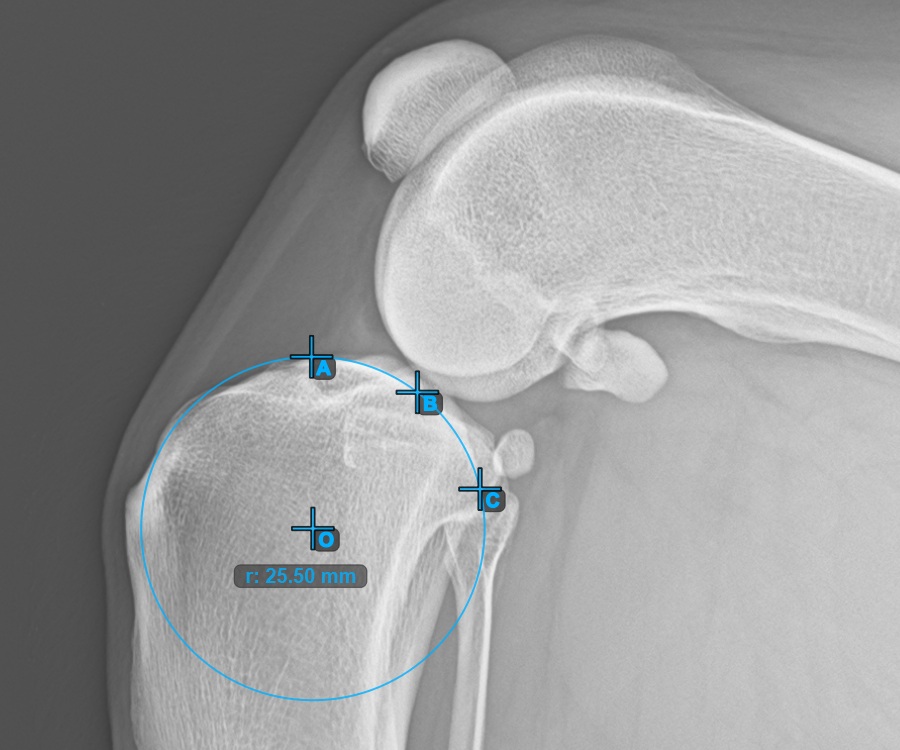

Start the measurement by marking the three points on the Condylus Medialis Tibialis.

Mark the three points on the main condylus of the tibial bone (Medialis Tibialis). Regardless of the order, make sure to mark the most cranial point, the most caudal point and the midpoint of the Medialis Tibialis. A circle will be automatically constructed based on the three placed points.

The image below represents a typical placement of the three points on the Condylus Medialis Tibialis.